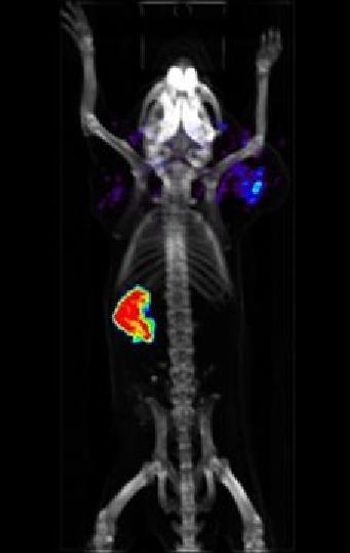

They are nearly microscopic, yet ganged together they can pack a big punch. They are microbeads embedded with radioisotopes and infused into body parts containing cancer tumors. The idea is to surround and destroy the tumor. The problem is making sure the microbeads stay put. SPECT/CT can provide the information to make it work.